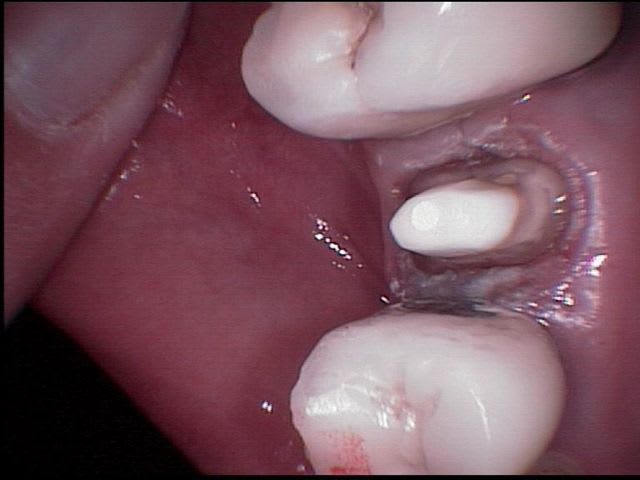

le problème ici c'est la non temporisation entre la reprise du traitement endo et la finalisation de la prothèse.

je ne critique absolument pas ce qui a ete fait, mais comment savoir que le retraitement va donner satisfaction? la lésion est peut être due a un sous traitement mais aussi bien a une anatomie canalaire particulière ou d'autres causes et meme si l'image radio semble bonne je pense que 2 mois sous provisoire afin d'objectiver radiologiquement une réussite de la réobturation aurait été plus sécurisant.

Je ne prends pas ta réflexion pour une critique, ce que j'ai fait, je l'ai fait parce que j'ai 60 berges bientôt et que la seule consolation à cet âge canonique, c'est l'expérience que cela m'a apporté, j'utilise toujours cette démarche lorsque je peux assécher le canal et ce fût, en l'occurence, le cas.

Si jamais il y a un problème, il sera toujours temps de faire un résection apicale, les couronnes temp pendant plusieurs mois ne me font pas réver.